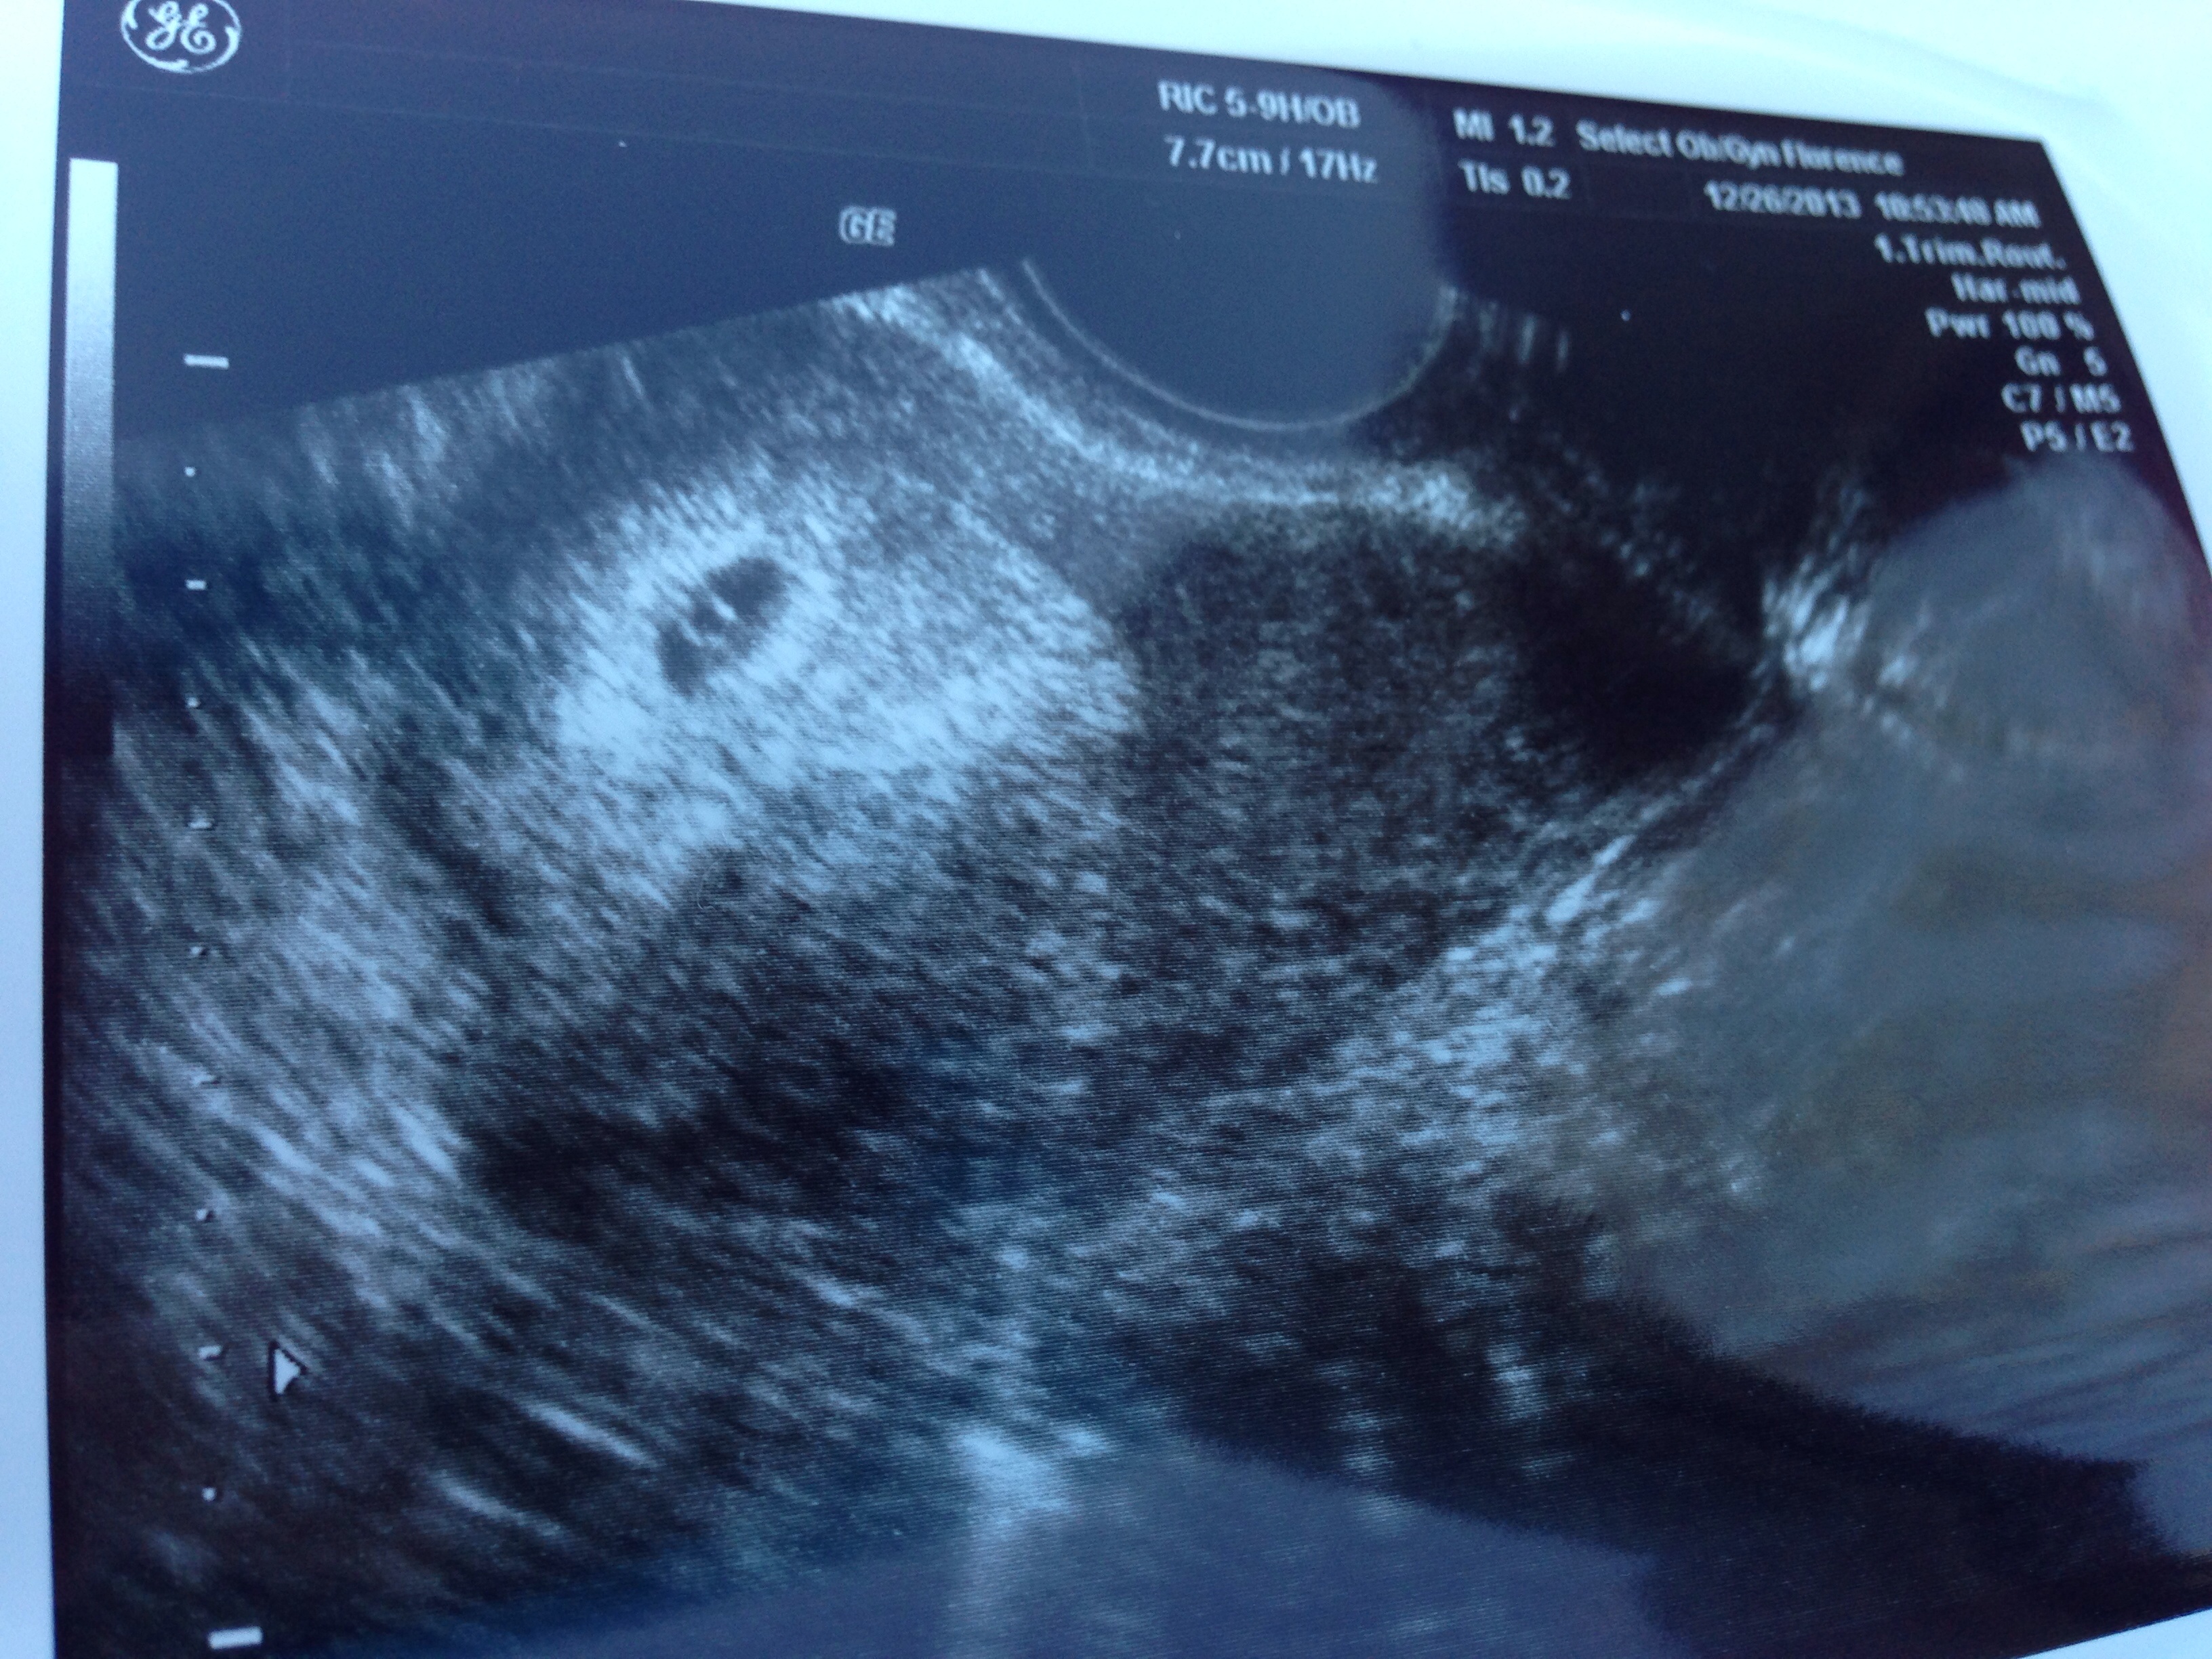

6 week us pic

So far so good

Looks good, congrats Mama!

congrats! any HB yet?

Not yet.. Still early.. Next us jan 10